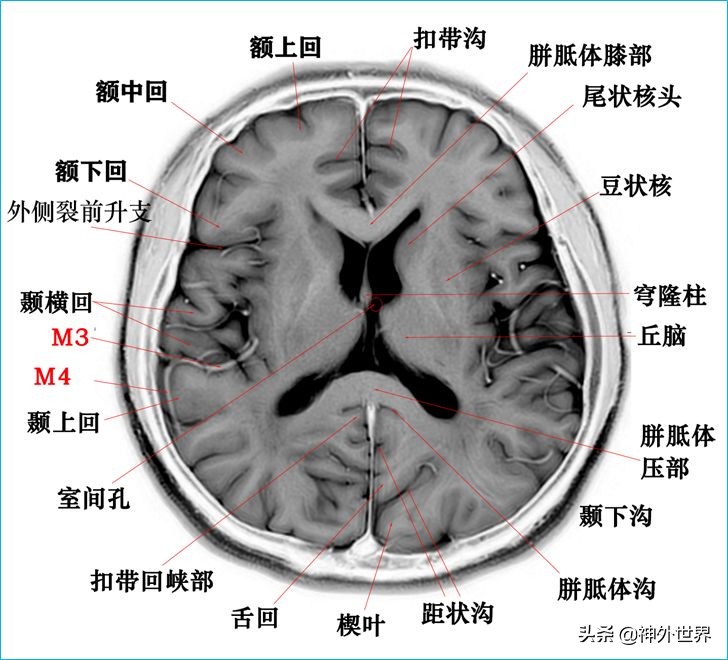

四、T2WI反相图学颅脑断层解剖

以下图片均来自我院3.0T核磁共振的T2WI反相图。标注均为我自己完成,水平有限,难免有误,还望各位老师多多指正。谢谢。